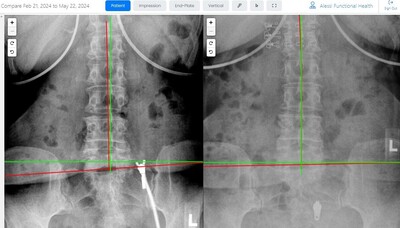

Results You Can See... and Feel!